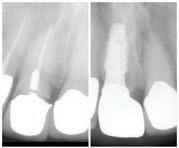

제거할 수 있나요?

집에서 관리하는 것만으로도 완벽하게 하얀 미소를 유지할 수 있으면 얼마나

좋을까요? 불행히도 플라크 (plaque) 같은 문제는 구강 건강 루틴의 늘 숙제요.

Christopher Chung, DMD Smile Again Dental Group 818-776-9300 트와 같은 치석 제거 제품이나 딸기, 식초, 참깨와 같은 "천연" 치료법이 알려 져 있어 유혹 당하기 쉽고, 이러한 재료와 제품은 지역 식료품점이나 약국에

플라크와 치석이 무엇인지, 플라크 형성을 예방하는 데 있어 어떤 역할을 할

수 있는지, 또 플라크를 제거하는 것이 왜 가장 안전하고 현명한 선택인지 알

아보겠습니다.

박테리아와 설탕으로 이루어진 끈적끈적한 물질인 플라크는 굳어져 치석으

로 변할 수 있습니다. 치석은 구강 건강에 부정적인 영향을 미칠 수 있으므로

이를 예방하는 것이 중요합니다.

집에서 치석을 제거할 수 있나요?

치과의 도움 없이 치아에서 치석을 제거하는 방법이 궁금할 수도 있지만, 깨

끗하고 정확한 작업을 위해서는 치과의사의 도움을 받는 것이 가장 좋습니

다! 플라크가 치석으로 굳어지면 칫솔로는 제거할 수 없습니다. 치과 도구 키

서 쉽게 구할 수 있지만, 집에서 하는 방법보다는 치석 제거에 대해 치과 의사

와 상담하여 더 효과적이고 건강한 방법으로 제거하는 것을 권장합니다.

치석이 구강 건강에 미치는 영향

치석이 치아와 잇몸선을 따라 쌓이면 구강 건강 문제가 발생할 수 있습니다.

치석은 치아에 플라크가 부착될 수 있는 영역을 제공합니다. 그래서 그것이

쌓이면서 더 많은 치석을 생성하는 치석에 플라크가 달라붙는 순환이 시작됩 니다. 플라크는 잇몸 질환 및 충치와 같은 질환을 유발할 수 있으므로 이러한 플라크에서 치석으로의 순환이 발생하지 않도록 하는 것이 가장 좋습니다.

잇몸선 주변에 치석이 쌓이면 잇몸 염증과 출혈이 발생할 수 있습니다. 잇몸

질환의 초기 단계인 치은염입니다.

치석은 미용적인 문제도 일으킬 수 있습니다. 치석은 흡수성이 있기 때문에

얼룩이 빨리 스며들 수 있습니다. 즉, 차나 커피와 같은 색소 음료를 마시면

치아가 어두워져 누런 미소를 지을 수 있다는 의미입니다.

치석이 쌓였는지 아는 방법

치석이 쌓였는지 판단할 때 치아의 느낌을 보면 알 수 있을 것입니다. 치석은

칫솔질만으로는 제거되지 않는 입안의 거친 물질처럼 느껴집니다.

치석이 잇몸선 아래에 나타나면 출혈이 발생할 수 있는 부기가 증가할 수 있 습니다.

잇몸선 위의 축적물은 노란색 또는 황갈색이며 제거하지 않으면 더 커집니 다. 잇몸선 아래는 갈색이거나 검은색일 수 있습니다.

치석 축적을 예방하는 방법

많은 치과 문제와 마찬가지로 해결책은 대개 예방에 있습니다! 전문적으로

제거해야 하는 치석 축적 단계에 도달하기보다는 애초에 치석 축적을 방지하

기 위한 조치를 취할 수 있습니다.

집에서 안전하게 치석을 제거할 수는 없지만, 철저한 구강 위생 관리를 통해

다음 단계에 따라 플라크를 제거할 수 있습니다.

하루에 두 번씩 부드러운 칫솔로 이를 닦으세요.

칫솔은 치아와 잇몸 표면 전체에 닿을 수 없으므로 하루에 한 번 치실을 사용 하는 것을 잊지 마세요.

기존의 치실을 사용하는 데 어려움이 있는 경우 치간 칫솔이나 워터 플로스 같은 대체 도구에 대해 치과위생사 에게 문의하세요.

양치 후 불소 구강청정제로 입안을 헹구어 놓친 박테리아 축적물을 제거하세

요. 양치질과 치실 사용 습관이 양호하더라도 정기적으로 치과 전문의에게

검진을 받는 것을 권장합니다.

치석

제거엔 치과방문이 최고인 이유

치석을 제거하려면 생각보다 더 많은 교육과 구체적인 훈련이 필요합니다.

미국치과협회(American Dental Association)에 따르면 치과위생사는 일반적으

로 치아를 제대로 닦기 위해 최소 2년 동안 공부합니다. 그 외에도 치과 위생

학사 및 석사 학위도 있습니다. 교육은 제쳐두고, 날카롭거나 부적절한 도구

를 입에 넣는 사람은 치아나 잇몸을 쉽게 손상시킬 수 있습니다. 자신의 구강

상태를 누구보다 잘 안다고 생각할 수도 있지만, 안전한 치석 제거에 대한 책

이를 수행합니다. 합리적인 가격 때문에 전문가의 도움을 기피하는 일 이 없도록 하세요. 비용이 문제라면 치과 및 치과 위생 학교와 같이 저렴한 치 과를 선택할 수 있는 옵션이 많이 있습니다. 이러한 임상 시설에서 지도를 받 는 학생들은 임상 경험을 얻기 위해 저렴한 비용으로 진료를 제공합니다.

임은 담당 치과의사가 맡아야 합니다. 스케일링이라는 수동 스케일링 도구나 초음파 장치를 사용하는 프로세스를